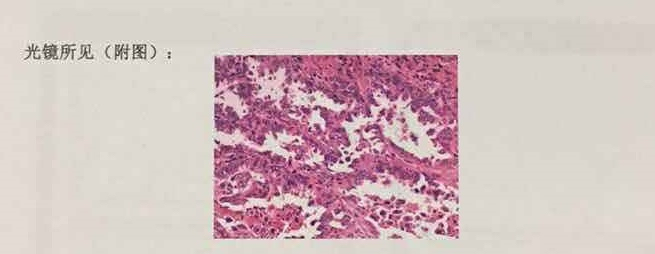

3、镜下所见

这一部分内容大多只有几副图片,为镜下所见符合肺癌典型病理特征的区域以及其他随检组织的切片图。